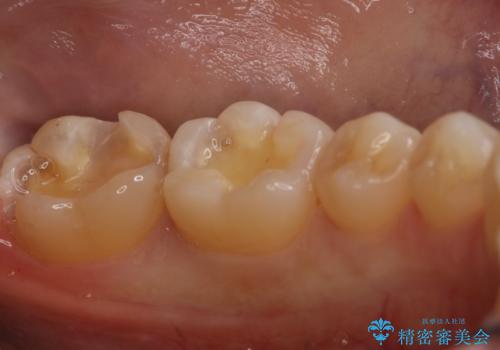

- 左下6、7番の虫歯をセラミックにて治療を希望された患者様です。

切削量を考慮してセラミックインレーを選択しました。

- 154,000円(2本分)費用は治療当時の料金となります